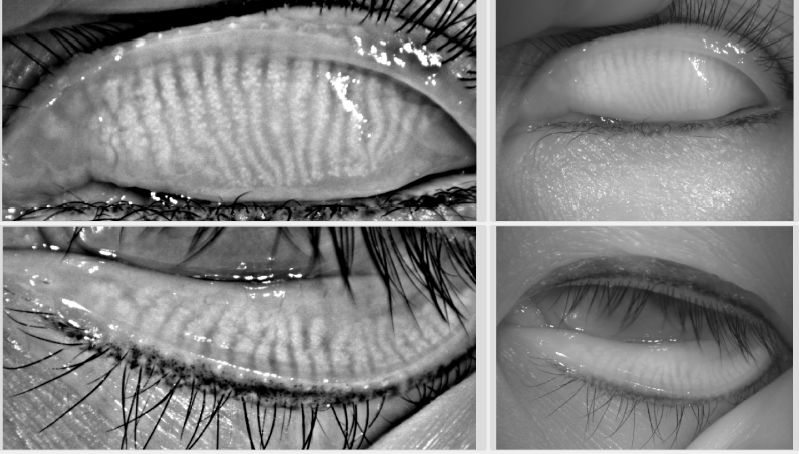

(圖一)正常的睑闆腺